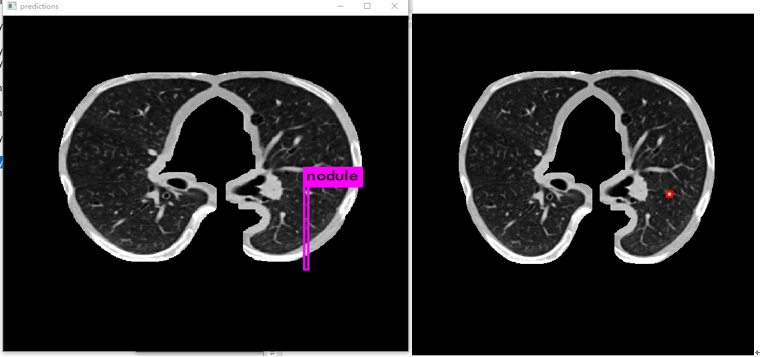

3. 检测效果预览

3.2 训练结果显示

原图:

预测:

标注图(根据标注生成):

在应用yolov3算法进行肺结节检测时,发现其在实际应用中仍存在一定局限性。具体表现为:1)迭代训练不足导致模型尚未达到充分收敛的状态;2)有必要对训练数据集进行聚类分析以优化参数设置,并调整anchor框大小与比例参数设置以进一步提升检测精度。